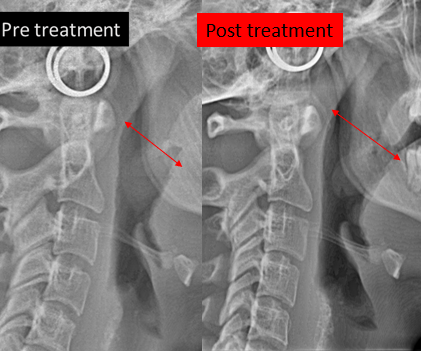

Obstructive Sleep Apnea (OSA) is a sleep-related breathing disorder commonly associated with a narrow upper jaw that restricts airway space. MARPE helps by expanding the maxilla, thereby widening the nasal cavity and upper airway.

As the palate expands, nasal resistance decreases and the tongue gains more space to rest in a proper position. This can reduce airway collapse during sleep, leading to improved airflow, reduced snoring, and better sleep quality. While MARPE is not a complete cure for cases of sleep apnea, it can play a valuable role in the comprehensive management of sleep-related breathing disorders.